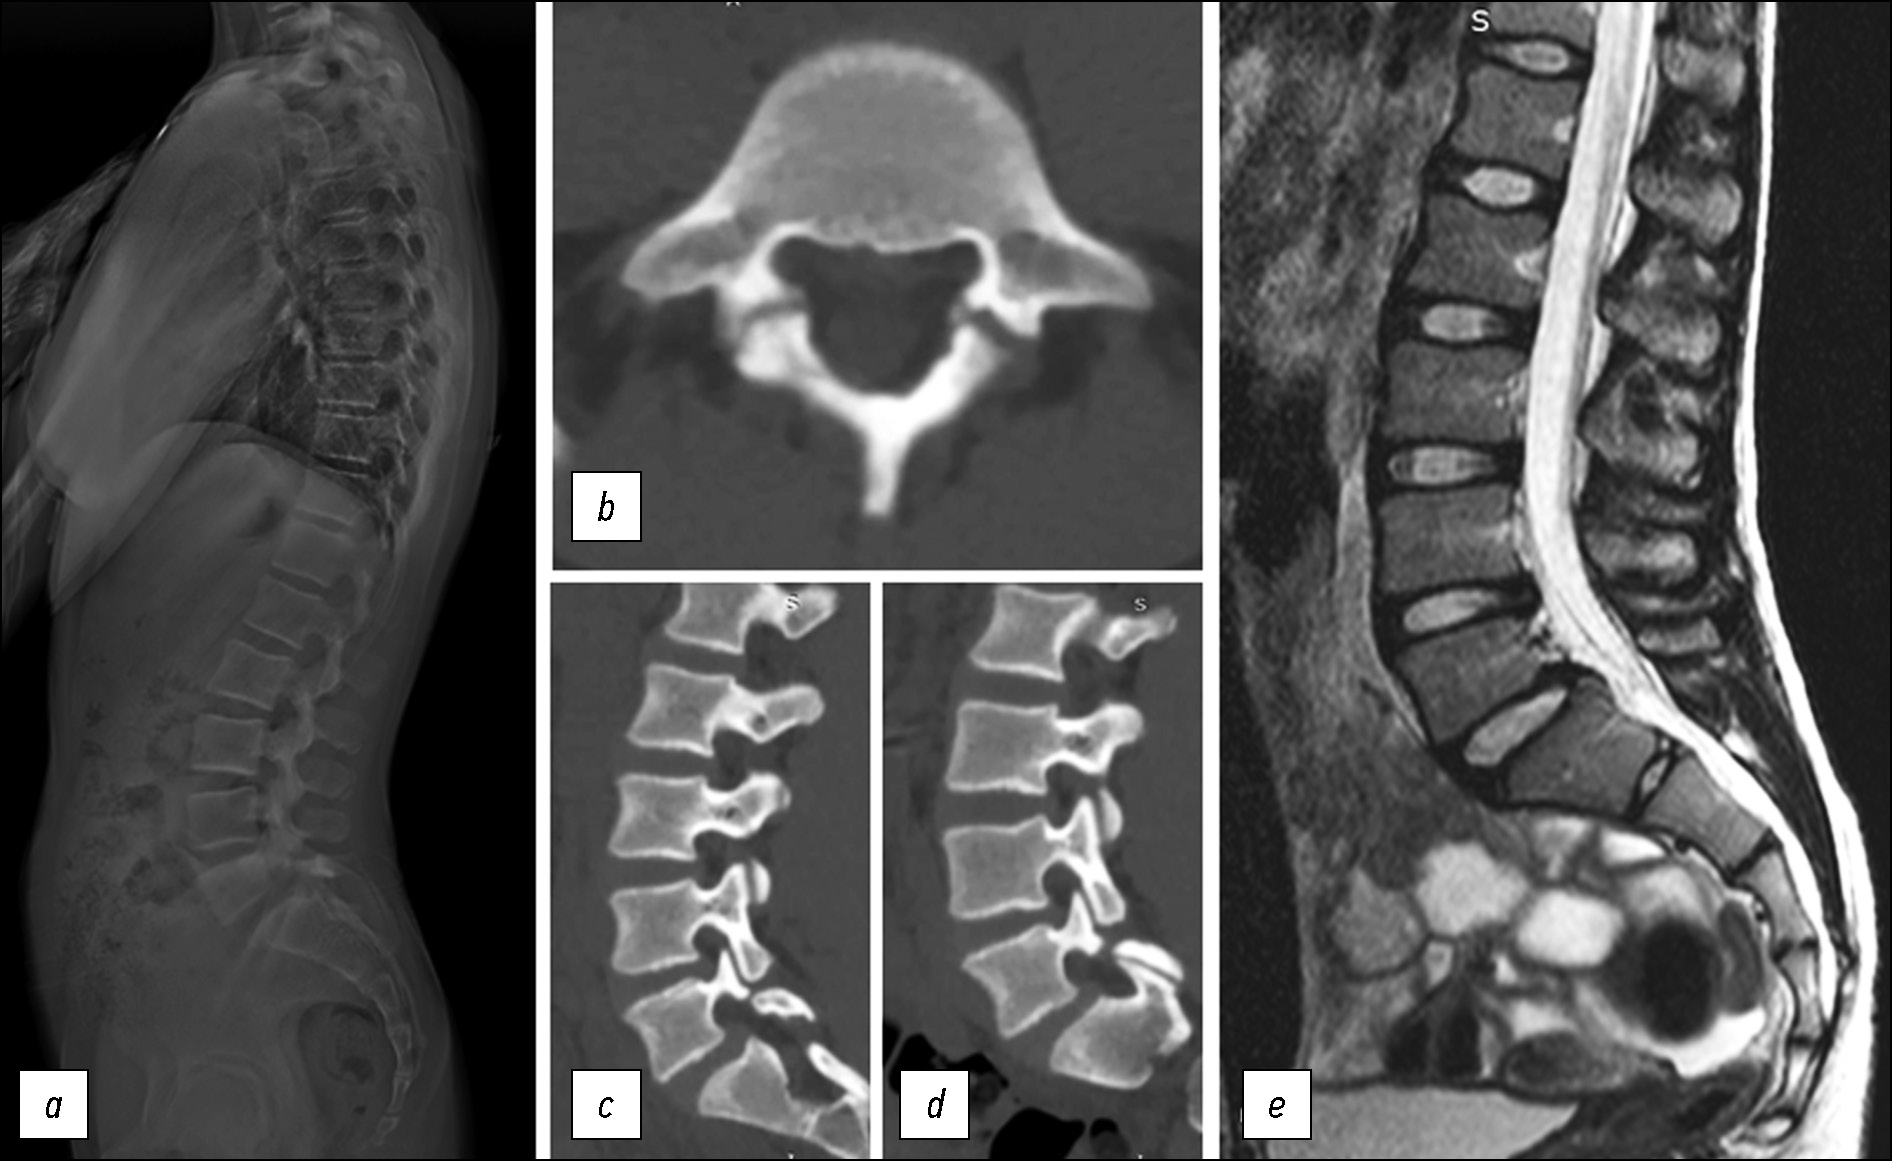

На контрольных КТ и постуральных рентгенограммах через 2 года — положение конструкции правильное, фиксация зоны спондилолиза стабильная, по данным КТ определяются лишь незначительные участки консолидации зон спондилолиза, полное сращение с закрытием спондилолизных дефектов отсутствует (рис. 6).

Рис. 6. Отдалённый результат через 2 года (положение конструкции правильное, фиксация зоны спондилолиза стабильная): а, b — рентгенография при сгибании и разгибании туловища — движения в сегменте L5-S1 сохранены, с — объёмная реконструкция компьютерной томографии, d, e, f — признаки лишь частичного сращения зон спондилолиза.

Fig. 6. 2 years follow-up (implant position is correct, fixation is stable): a, b — radiography flexion and extension X-ray, motion on L5-S1 level is preserved, c — CT reconstruction, d, e, f — absents of complete fusion of spondylolysis defects, fixation is stable.

Через 1 месяц осуществлён контрольный осмотр. Пациентка уже приступила к умеренным физическим нагрузкам в гимнастическом зале, однако отмечала незначительный болевой синдром в поясничном отделе (2 балла по VAS). По данным рентгенографии, положение металлоконструкции корректное. Движения в поясничном отделе позвоночника в полном объёме (рис. 5).

Через 3 месяца с момента операции пациентка возобновила тренировочный процесс в полном объёме и приняла участие в соревнованиях. Болевых ощущений в поясничном отделе позвоночника не отмечает (Ped`s QL — 98 баллов, ODI — 10%, VAS — 0 баллов). Через 6 месяцев после операции прошла все квалификационные испытания и получила звание «мастер спорта», выступала на Чемпионате России и Кубке России по спортивной гимнастике.